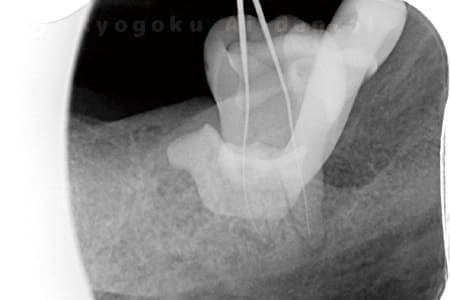

ニッケルチタンファイルの使用

通常の保険診療ではステンレスのファイルを使用します。しかし、根管の内は常に真っ直ぐとは限りません。人によって千差万別で不規則に曲がっている場合がほとんどです。

そうした根管の先端まで確実に治療するには、弾性のあるニッケルチタン製のファイルを使う必要があります。

保険診療のステンレス製のファイルは弾力性がないので、曲がった根管内の治療には限界があるのも事実です。

ニッケルチタンファイルを使用することで治療の成功率を向上することができます。